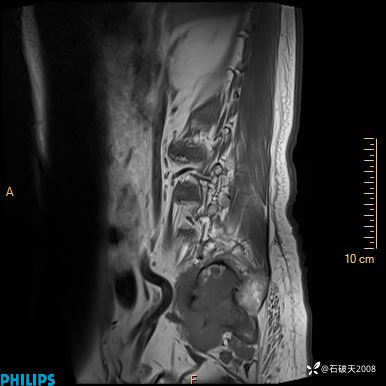

2023年3月份MRI影像

T2矢状位